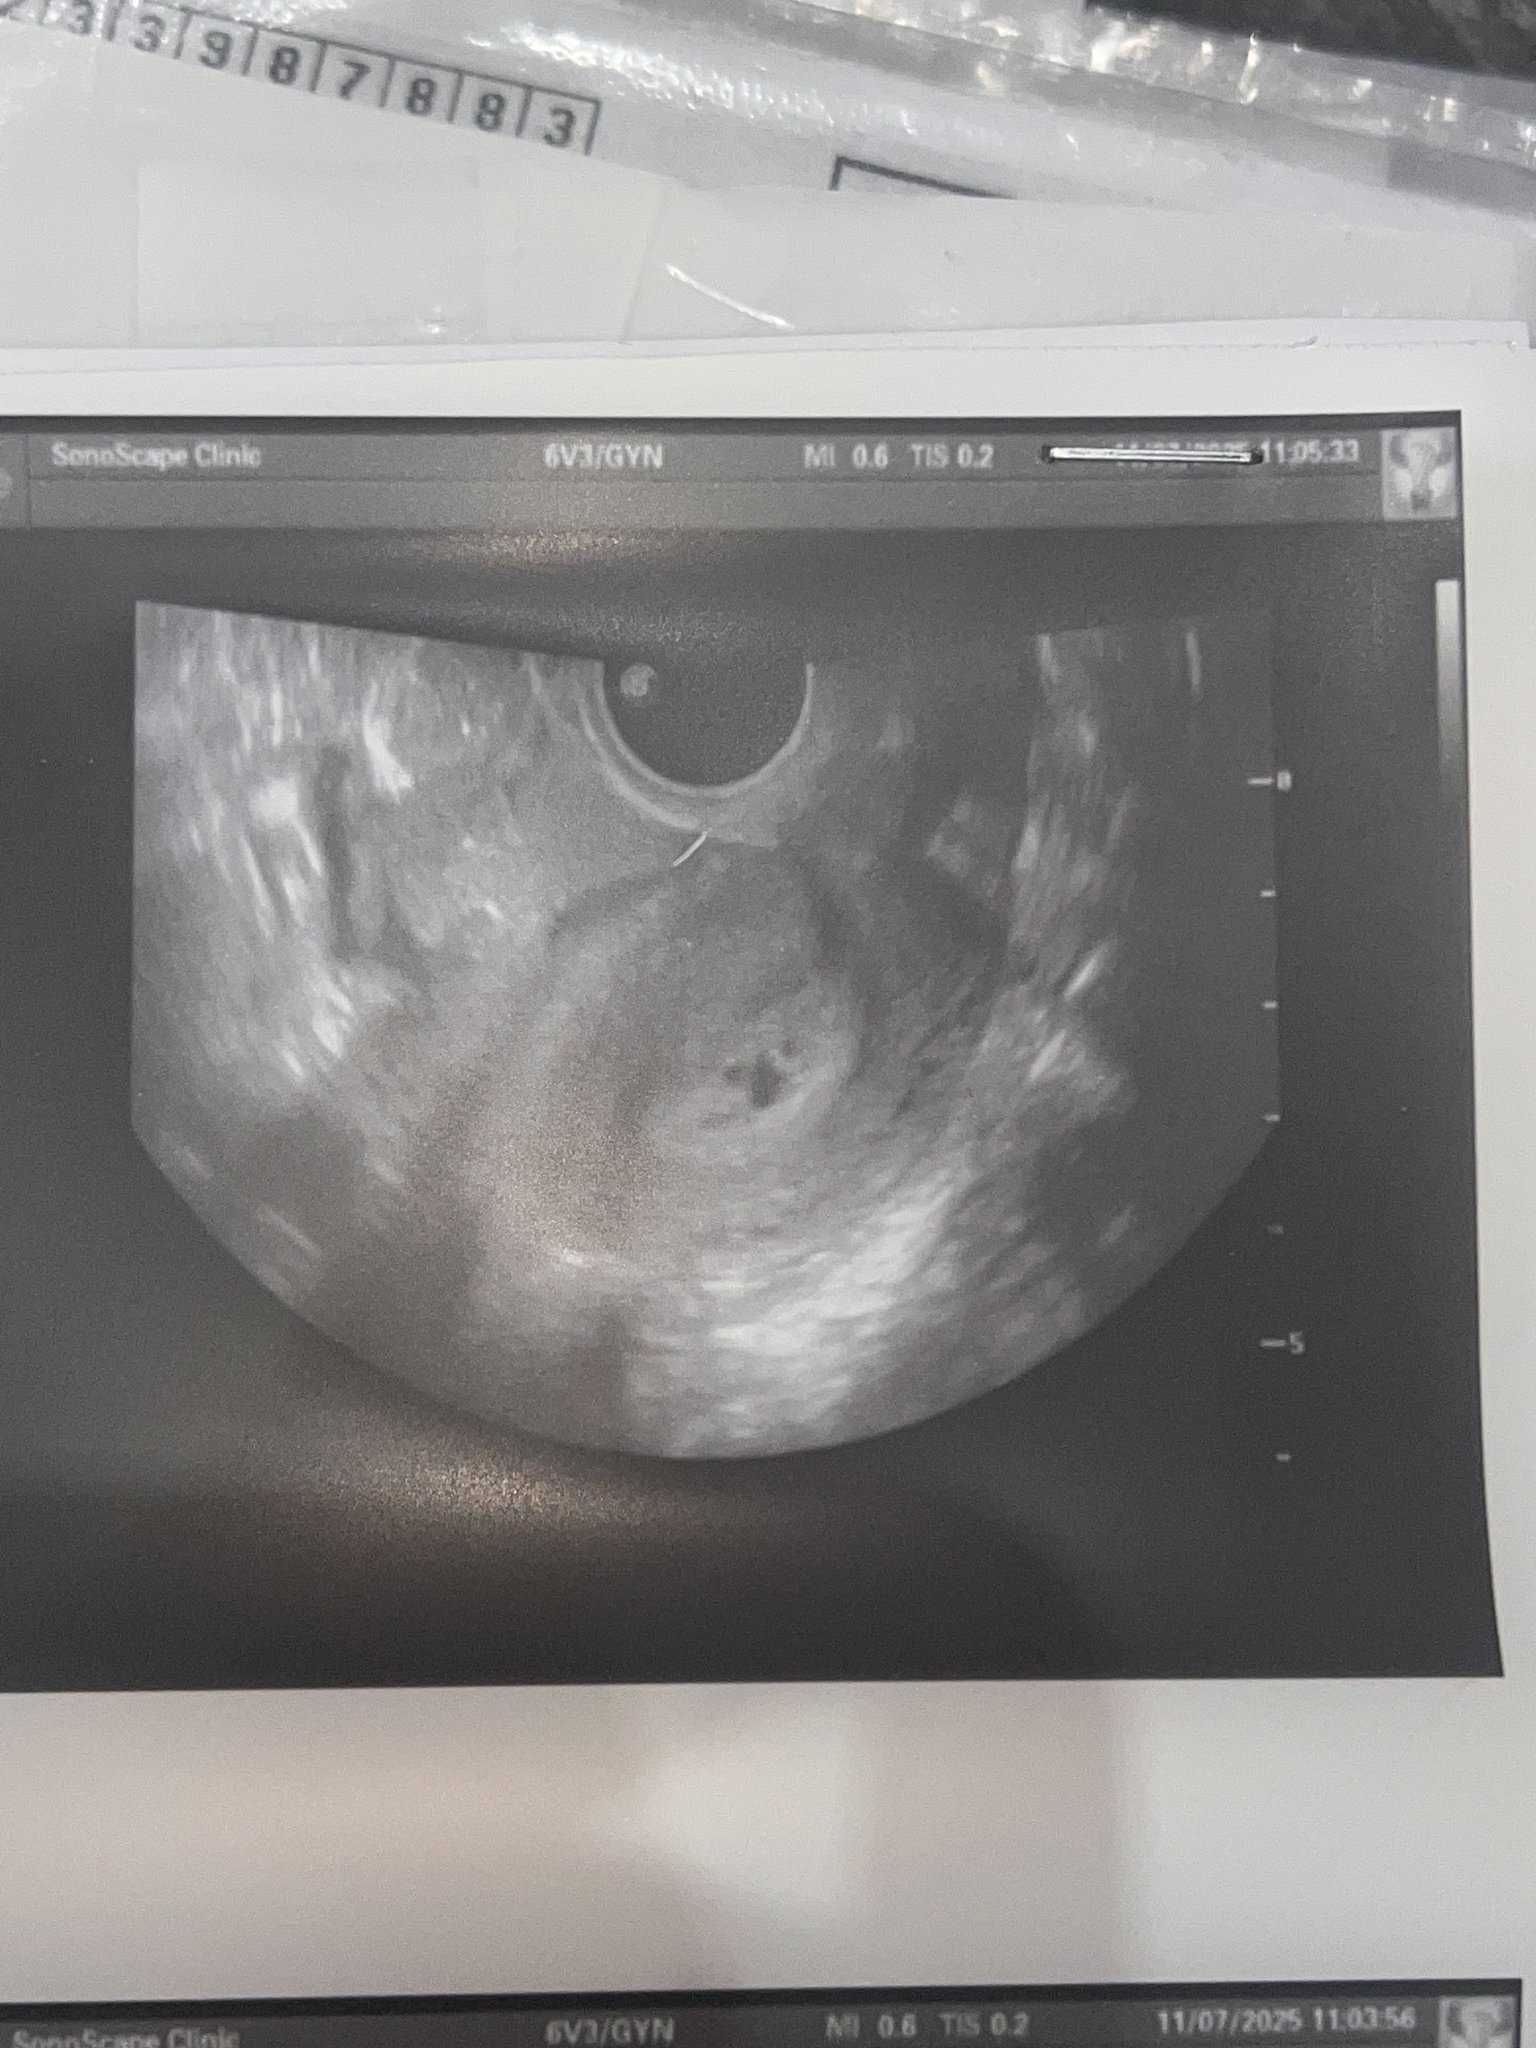

Какво представлява изображението от ехографията на 5-седмична и 2-дневна бременност?